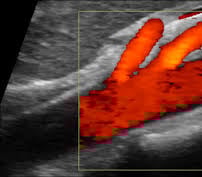

A Mesenteric artery ultrasound, also known as mesenteric duplex, is performed to assess blood flow to the intestines and other abdominal organs. It helps diagnose and monitor conditions like mesenteric artery stenosis (narrowing) or aneurysms. The Doppler ultrasound can measure blood flow velocity in the arteries, helping to identify areas of restricted flow.

Mesenteric arteries are relatively small and located deep within the abdomen, making them challenging to visualize and interrogate with ultrasound. An experienced sonographer is crucial for mesenteric artery ultrasounds due to the technical complexity of imaging these vessels and the need for accurate interpretation of Doppler waveforms. Accurate diagnosis relies on understanding normal and abnormal flow patterns and correctly identifying normal variants, which requires specialized expertise.